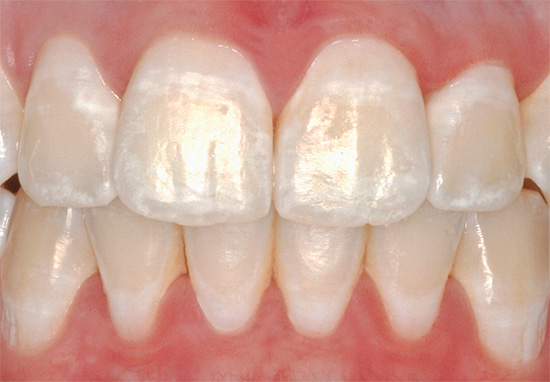

La carie viene mostrata nella prima fase di sviluppo quando si tratta di un punto bianco o gessoso (ecco come appaiono le aree dello smalto demineralizzato):

È interessante notare che nella fase della fase della carie, la maggior parte delle persone non presta alcuna attenzione: pensa, il dente ha leggermente cambiato colore, non sai mai cosa c'è di sbagliato in esso. Ma invano, perché in questa fase la carie può ancora essere curata senza trapano, riempimento e violazione dell'integrità dei tessuti di un dente vivo. Se perdi un momento, quindi senza installare un sigillo (nella migliore delle ipotesi) è improbabile che tu possa già farlo.

Ad esempio, ecco i denti anteriori con macchie bianche nella foto - i fuochi della carie iniziale: